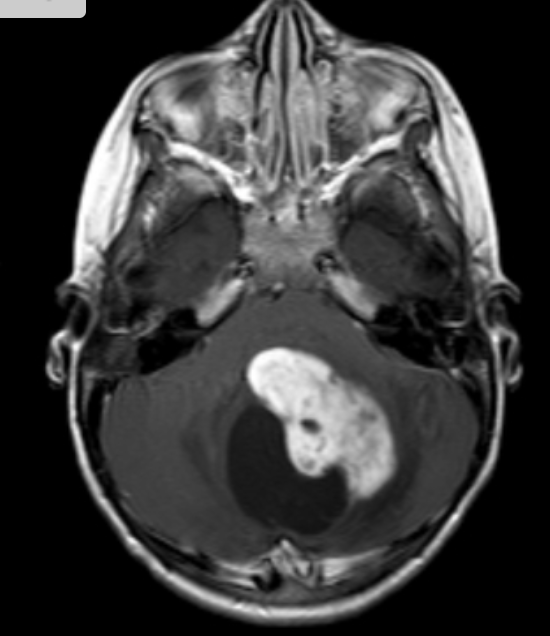

Immunocomprimised : Fulminant CNS disease. Basal ganglia, Corticomedullary junction. solitary or multiple ring enhancing lesions with marked surrounding edema. Eccentric target appearance. After treatment lesions may calcify or haemorrage.

Most common CNS infection in HIV patients.

Caused by Toxoplasma gondii.

Reservoir in CATS.

3 Manifesations:

Congenital: meningitis, encephalitis, calcifcation, chorioretinitis, atrophy.

Immunocompetent: Systemic disease with LAD, fever, no CNS involvement.